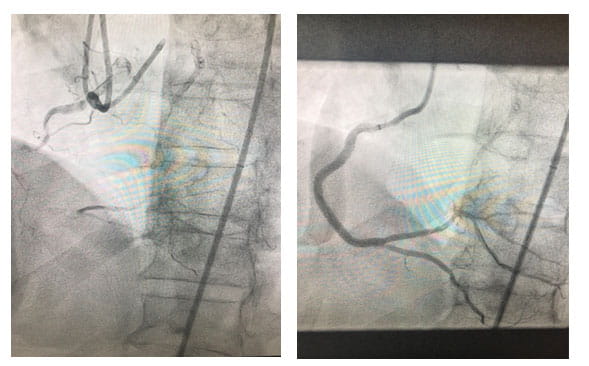

For patients with chronic total occlusion (CTO), a multi-site program stemming from University Hospitals Cleveland Medical Center has demonstrated an annual revascularization success rate of 85 to 90 percent over the past three years.

Performing more than 60 CTO revascularizations per year, University Hospitals Harrington Heart & Vascular Institute is achieving a success rate well above the national average of 55 to 60 percent. Each case requires individual evaluation and precision technique. Often, the heart develops collateral arteries to compensate for the blockage, essentially creating its own bypass. "Sometimes, we actually have to go backwards through these collateral arteries to make a connection and place a stent to open the blockage," Dr. Poommipanit says.